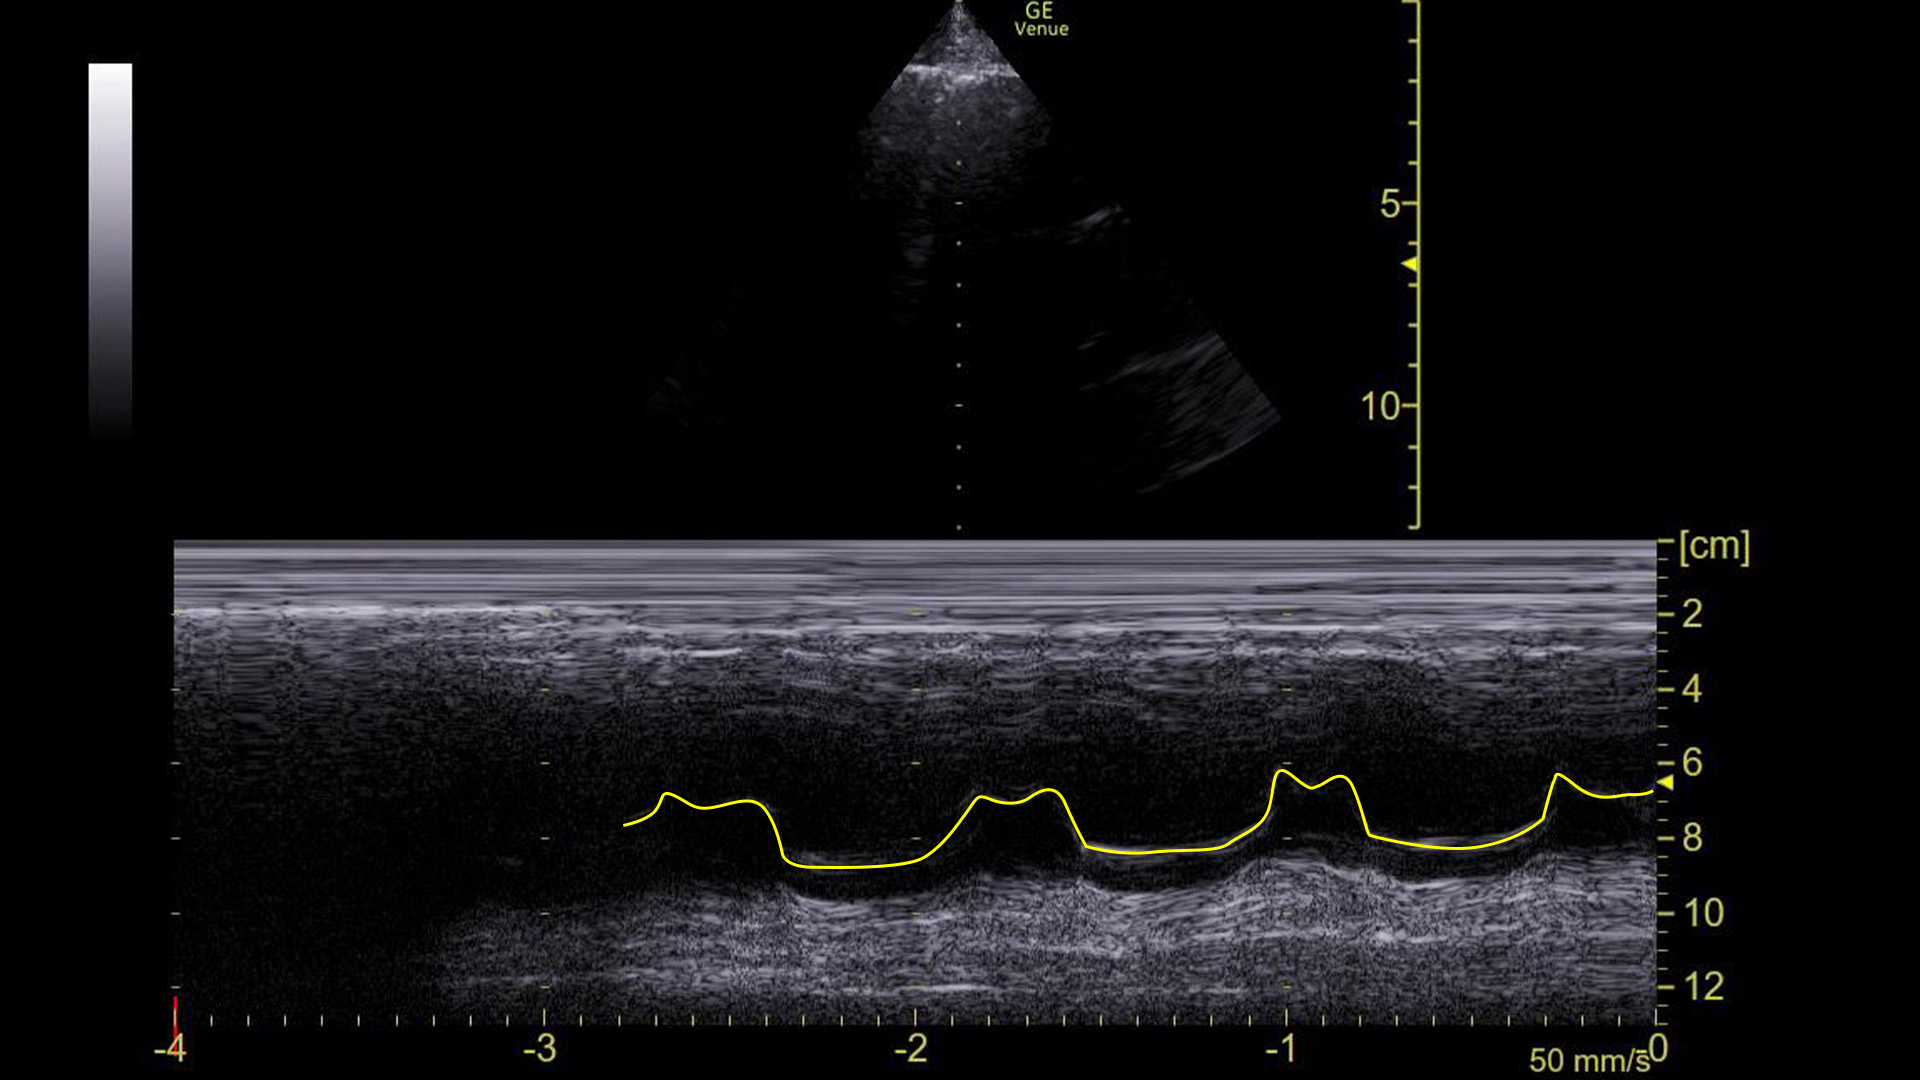

Here it is with the area of interest highlighted.

What we are looking at here is the movement of the mitral valve within the left ventricle – specifically what is highlighted in yellow is the movement of the anterior leaflet of the mitral valve. (Recall that it has two leaflets: anterior and posterior.)

You can see that the leaflet flaps once per cardiac contraction. That, however, is ABNORMAL!

We can see this on ultrasound as demonstrated above. Graphically on the screen, the first movement is called the E-wave, and the second is called the A-wave.

Compare that to the tracing before the cardioversion:

There are no A-waves.

This tells us that the atria are not contracting in an organized, functional way because the mitral valve is only flapping once during each heart beat.